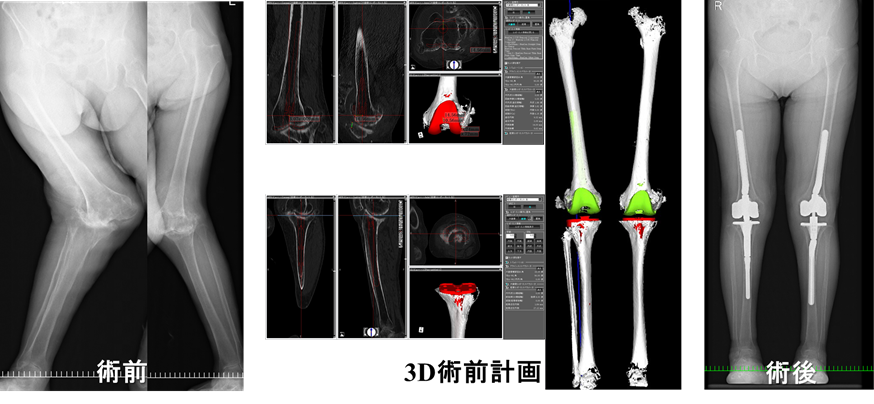

膝関節外科学: 書籍/南江堂。膝関節外科学 The Knee 膝関節外科学: 書籍/南江堂。膝関節外科 | 関西医科大学整形外科学講座 - Part 1000。膝関節に関する基礎から応用までを網羅した専門書。商品詳細ページ | メディカルブックセンター。- タイトル: 膝関節外科学- 出版社: 南江堂- 定価: 定価19,800円(税別18,000円)1度も読んでいない新品ですが素人の自宅保管になります。。中身は読んでいないので新品同様綺麗ですが、表紙やカバーには新品ですが保管による小傷や汚れがある場合がありますので完璧な新品を求めている方は落札をご遠慮下さい。在宅看護指導士 予想問題集 2025年度版 アプリなし。他にも多数出品しておりますので是非宜しくお願い致します。カンデル 神経科学 第2版 メディカルインターナショナル。